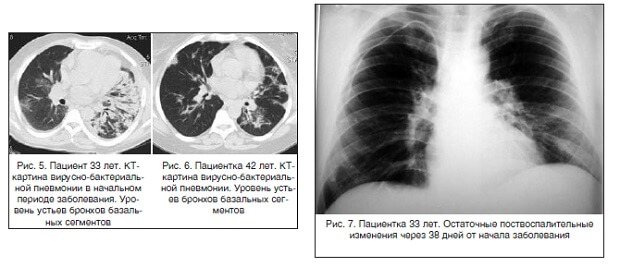

- Гораздо реже для дифференциальной диагностики или если признаки пневмонии на рентгене выявлены нечетко (например, вирусная пневмония, симптомы у детей которой стерты) могут назначить компьютерную томографию легких.

Главные симптомы пневмонии – кашель и затрудненное дыхание. При этом больной чувствует слабость и упадок сил. Из-за дыхательной недостаточности и гипоксии его кожа может приобретать бледный или синюшный оттенок. Ниже представлены фотографии пациента с пневмонией и рентгеновский снимок легких: